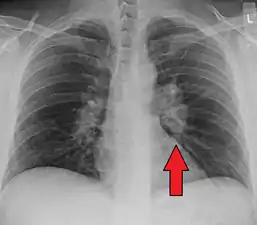

| Chest X-ray showing the typical nodularity of sarcoidosis, predominantly in the hila of the lungs. | |

Hilar adenopathy especially on the person's left (AP CXR)